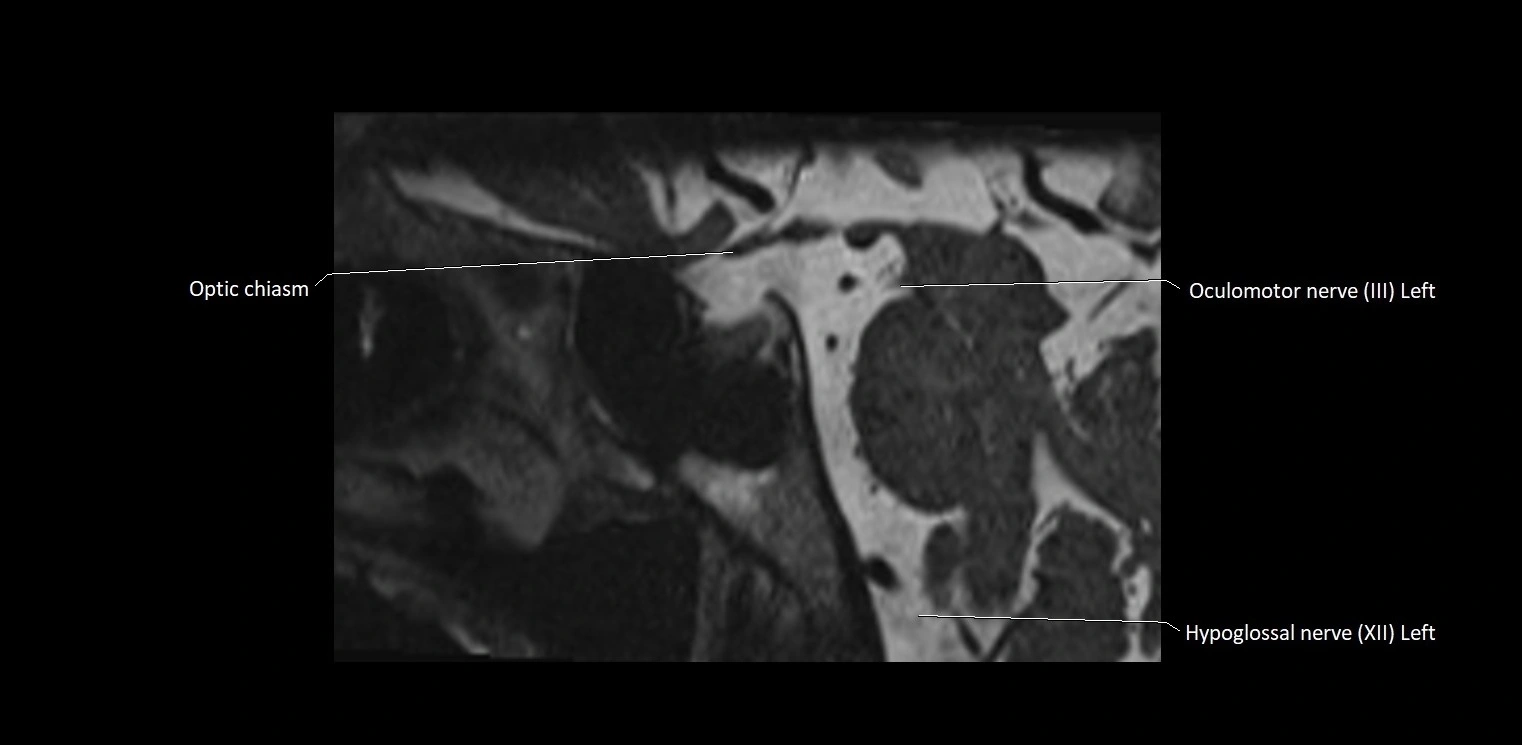

MRI Appearance

• The abducens nerve is a small, thin, linear structure

• Best visualized on high-resolution T2-weighted 3D MRI sequences (e.g., FIESTA or CISS)

• Seen as a hypointense (dark) line running from the brainstem at the pontomedullary junction, traversing the prepontine cistern, and entering Dorello’s canal under the petrosphenoidal ligament, then into the cavernous sinus, and finally the orbit

• May be challenging to visualize in standard MRI due to its small size

• Pathology may be inferred by absence, displacement, or enhancement of the nerve

MRI images

image